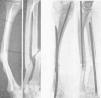

Figura 4. Enclavijamiento mixto en una pseudoartrosis de cúbito y radio, previo refrescamiento de fragmento. Fue utilizado alambre en cúbito por no disponer entonces de tallo suficientemente largo. La misma, una vez obtenida la consolidación.

Figura 5. Fractura doble, antebrazo; enclavijamiento cerrado con alambres.

Figura 6. Fractura espiroidea tibia y conminuta peroné, que ni la extensión continua mantenía reducida. Enclavijamiento cerrado de la misma. La misma, consolidada.